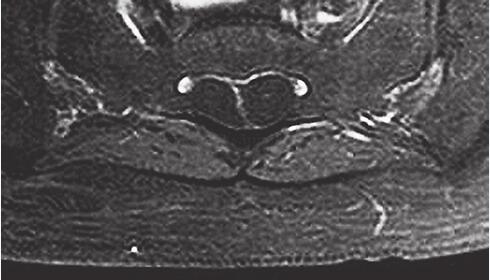

增强腰椎MRI:双侧马尾神经根增粗,明显强化。椎管内可见多发椭圆形液体信号影,边界清楚,增强后囊壁轻度强化。双侧髂腰肌,臀大肌萎缩并脂肪变性。椎间盘未见异常。诊断:双侧马尾神经根炎,骶管囊肿,压迫神经根(图31-2)。肌肉MRI显示:大腿后部肌群萎缩,磷谱提示神经源性肌代谢异常。

图31-2 腰椎MRI增强:轴位T1WI压脂像显示双侧马尾神经根稍增粗,囊壁轻度强化